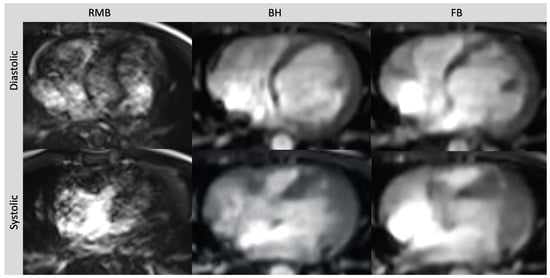

Figure 2.

Axial slices of all three cine sequences in systolic and diastolic phases in a patient with severe arrhythmia. Severe artifacts in RMB rendering volumetric evaluation insufficient. Image quality in FB and BH images is reduced but still diagnostic. Retrospective segmented multi-breath hold (RMB), real-time single/double breath hold (BH), real-time free breathing (FB).

RMB relies on the regular periodicity of the heart rate to acquire data across multiple cardiac cycles, which are then merged to reconstruct a complete cine slice representing successive heartbeats. However, in the presence of arrhythmia, artifacts can occur due to the reconstruction using data from different phases of the cardiac cycle [27,28]. To mitigate this, arrhythmia rejection algorithms can be applied but may result in exceedingly long breath holds [29]. By incorporating parallel imaging, CS can achieve acceleration rates that enable real-time cardiac cine imaging. This helps to avoid misreferencing of the image data throughout the cardiac cycle [30]. Within our patient collective, we encountered a single patient who experienced non-diagnostic image quality in RMB due to artifacts related to arrhythmia. In this particular patient, ventricular volumetry was not feasible in RMB, whereas both CS sequences consistently provided diagnostic image quality, overcoming the challenges posed by arrhythmia-related artifacts (Figure 2). This is in line with several other studies that have demonstrated the superiority of real-time cine CS MRI images over retrospective gated acquisitions in patients with arrhythmia. In a study conducted by Longère et al. involving a cohort of 71 patients with arrhythmia, the implementation of compressed sensing real-time cine drastically reduced artifacts associated with arrhythmia. As a result, there was a marked improvement in the quality of cine images [29]. In a different study, carried out by Laubrock et al., real-time cine CS imaging was found to enhance the quality of images in 29 patients with atrial fibrillation. Volumetric analysis was feasible, albeit with slightly lower values compared to RMB, and ejection fractions remained comparable [31].